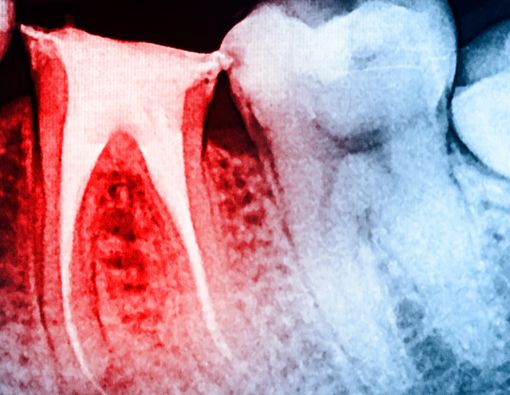

Gigi berlubang sering dibiarkan saja oleh penderitanya. Padahal, gigi berlubang yang diabaikan akan bertambah luas dan dalam hingga menembus rongga pulpa. Kondisi ini dapat menyebabkan infeksi saluran akar gigi.

Infeksi saluran akar gigi atau infeksi periapical biasanya timbul karena infeksi bakteri dari karies gigi yang tidak dirawat, trauma gigi, atau perawatan saluran akar yang gagal.

Hal tersebut terjadi akibat hilangnya lapisan pelindung gigi yang menyebabkan bakteri masuk, menekan dinding lapisan dentin di bawahnya, hingga mencapai rongga pulpa bagian dalam yang berisi jaringan ikat, pembuluh darah, dan saraf.

Infeksi saluran akar dapat menyebar ke jaringan di sekitar mulut, termasuk gigi, gusi, dan jaringan di pipi maupun wajah. Infeksi tidak akan hilang sampai diobati dan akan makin menyebar jika tetap tidak diatasi.

Pada kasus yang benar-benar parah, infeksi saluran akar yang tidak diobati bahkan dapat menyebar jauh ke rahang dan aliran darah.

Untuk mengatasinya, perawatan saluran akar dapat dipilih jika gigi masih bisa dipertahankan. Dokter gigi akan mengeluarkan semua nanah dari daerah yang terinfeksi sebelum atau saat melakukan perawatan saluran akar, serta memberikan antibiotik untuk mencegah infeksi lebih lanjut.

Kemudian, tingkat keparahan infeksi akan menentukan langkah selanjutnya. Jika infeksi berada di saluran gigi, cara yang paling umum dilakukan adalah melakukan perawatan saluran akar.

Fungsi perawatan saluran akar adalah membuang semua jaringan pulpa yang terinfeksi dan mencegah masuknya kembali mikroorganisme ke dalam saluran akar.